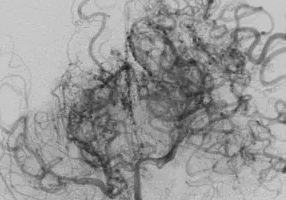

모야모야병은 뇌혈관 질환의 하나로, 뇌로 혈액을 공급하는 주요 동맥이 점차 좁아지면서 뇌에 산소와 영양 공급이 원활히 이루어지지 않는 희귀질환입니다. 이때 좁아진 혈관 주변에서 가느다란 새로운 혈관들이 생기는데, 뇌혈관 촬영 시 마치 연기가 피어오르는 듯한 모습으로 보이기 때문에 ‘모야모야’라는 이름이 붙었습니다. 주로 소아와 청년층에서 많이 발생하지만, 성인에게도 나타날 수 있습니다. 조기 발견과 치료가 늦어지면 뇌졸중이나 뇌출혈 같은 심각한 합병증으로 이어질 수 있어 원인과 증상을 이해하는 것이 매우 중요합니다.